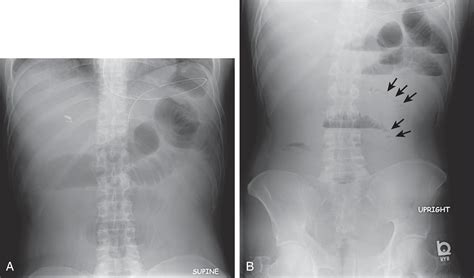

Feature Nonobstructive Pattern Obstructive Pattern

Gas Distribution Scattered throughout the small and large bowel. Localized to specific, dilated segments.

Bowel Diameter Within normal physiological limits. Significantly dilated (swollen).

Gas-Fluid Levels Minimal or absent. Prominent, indicating trapped air and liquid.

Clinical Implication Usually benign/functional issue. Requires immediate medical intervention.